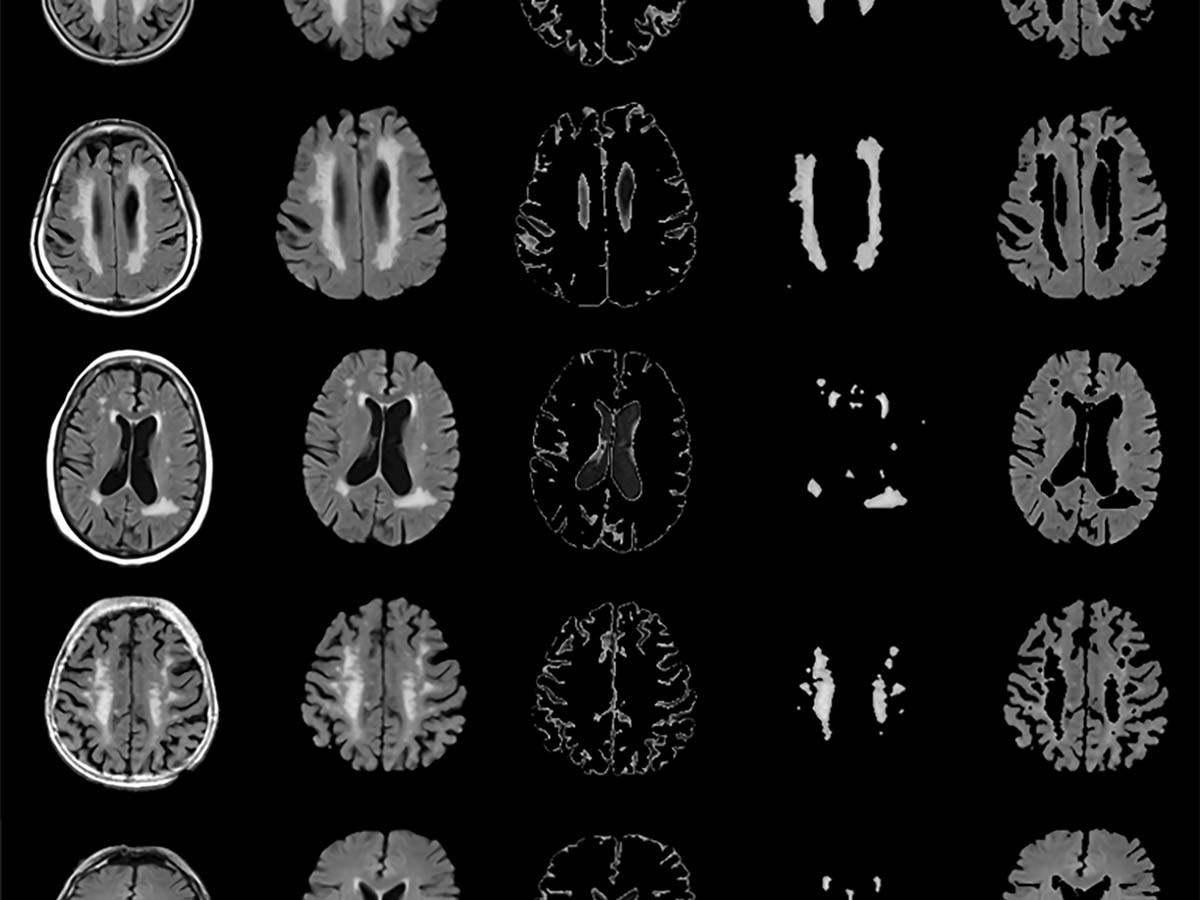

Brain health: Using AI in medical imaging to improve patient outcomes

Research that began during Toronto Metropolitan University (TMU) professor April Khademi’s PhD has resulted in a patented tool that can help transform how clinicians diagnose dementia and vascular disease, leading to earlier detection and improved patient outcomes.